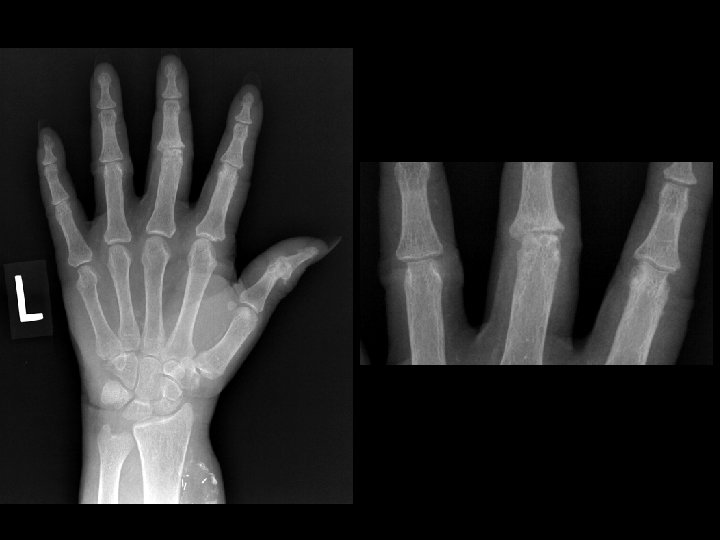

Dialysis arthropathy • Findings: – Multiple erosions on both sides of multiple PIP joints – Osteopenia, fuzzy trabecula, and dialysis graft = evidence of ESRD • ddx: – Inflammatory arthritis

Synovial chondromatosis • Findings: – Smoothly marginated erosions on both sides of the 4 th MCP joint – Soft tissue mass causing narrowing of the 4 th MC – Single joint involvement • ddx: – Rheumatoid – PVNS